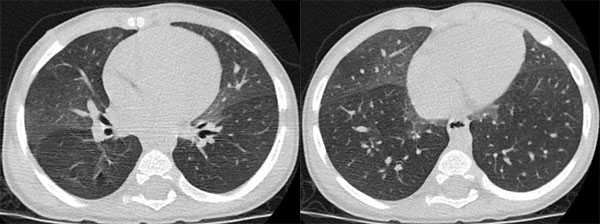

Фотографии, демонстрирующие обнаруженное усиление легочного рисунка

Раздел: Фотодневник открытий